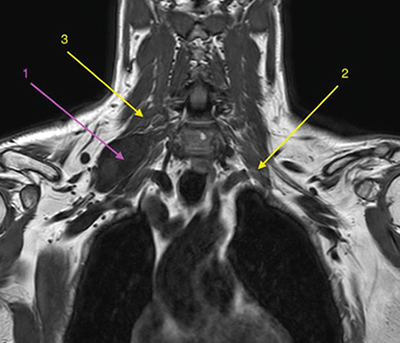

Figura 1

Los schwannomas de plexo braquial son tumoraciones desarrolladas a partir de las vainas neurales de rara presentación, pero evolución benigna. Pueden ocasionar clínica, generalmente de tipo neuropático, por crecimiento local con el consiguiente efecto compresivo de estructuras neurales nobles como las raíces del plexo braquial.

Presentamos el caso de un paciente diagnosticado de schwannoma de plexo braquial con efecto compresivo creciente, a quien se le plantea tratamiento con toxina botulínica en los músculos escalenos.